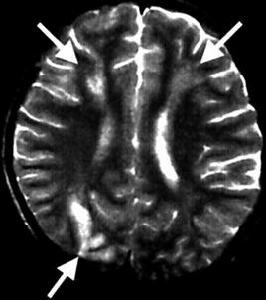

病理